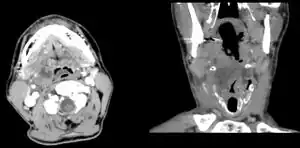

Diagnosis is usually based on the symptoms.[1] Medical imaging may be done to rule out complications.[1] Medical imaging may include CT scan, MRI, or ultrasound is also useful in diagnosis.[1]

Peritonsillar abscess on the person's right as seen on CT imaging